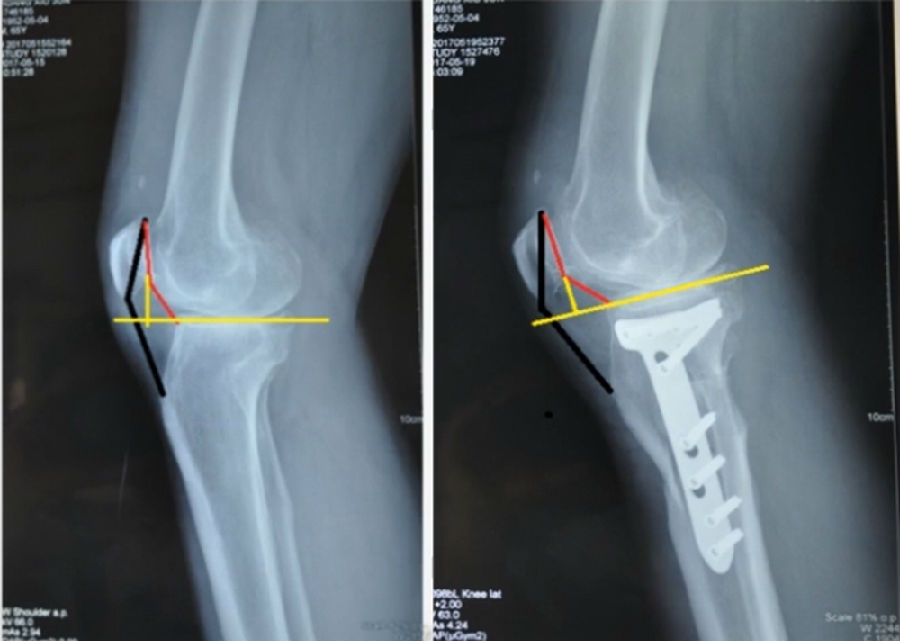

典型病例,女性,35岁,农民,左膝内翻、短缩、内旋。

术前

泰勒外固定架缓慢矫正短缩、内翻、前弓、内旋。

术中

该患者截骨后,做MAD矫正,目标MAD=0。患者术后1个月即达到设计的效果。

术后1个月

典型病例2,男性,52岁,双膝疼痛,低磷佝偻病,复合畸形。

股骨畸形即时矫正,胫骨畸形缓慢矫正。

手术前后对比

手术前后外观